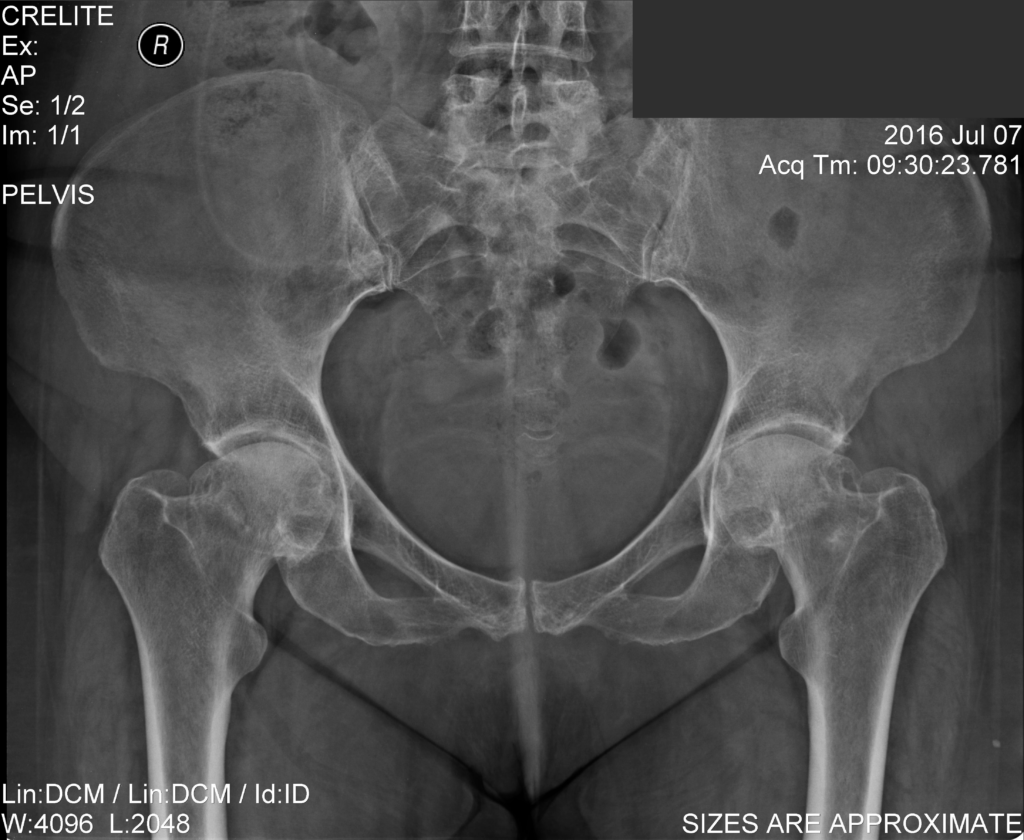

Ακτινογραφίες ασθενή ΠΡΙΝ την επέμβαση αμφοτερόπλευρης αρθροπλαστικής ισχίων